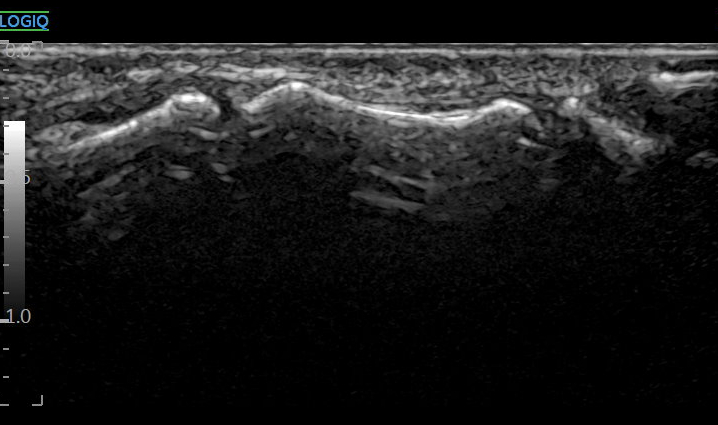

경혈 초음파 한의원

현대 한의학에서는

침 놓는 혈자리,

즉, 경혈을

눈으로만 보는 게 아니고요.

경혈 정밀 초음파를 함께 봅니다.

원래 표준 경혈 초음파상

뼈 표면(골 피질, Cortex)이

연결되어 보여야 하는데요.